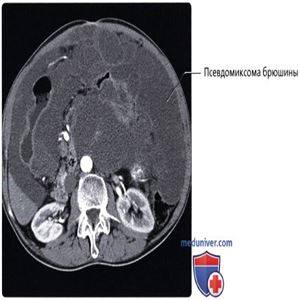

КТ с контрастированием, аксиальный срез: классическая картина псевдомиксомы брюшины: метастатическое поражение брюшины муцин-продуцирующей опухолью червеобразного отростка приводит к формированию скопления желатинообразного вещества в брюшинной полости. Формирование капсул и количество вещества обусловливают характерный масс-эффект, или вдавления, на внутренние органы полости живота и часто вызывают обструкцию кишечника.

КТ с контрастированием, аксиальный срез: у этого же пациента определяется сложный (с наличием перегородок) характер «асцитической жидкости», часто являющейся полужидким желатинообразным веществом. Метастазы наблюдаются по всей полости брюшины, включая метастазы, расположенные по поверхности печени, сальника и боковых каналов брюшной полости. Обратите внимание, что почки не подвержены влиянию опухоли благодаря своему забрюшинному положению.